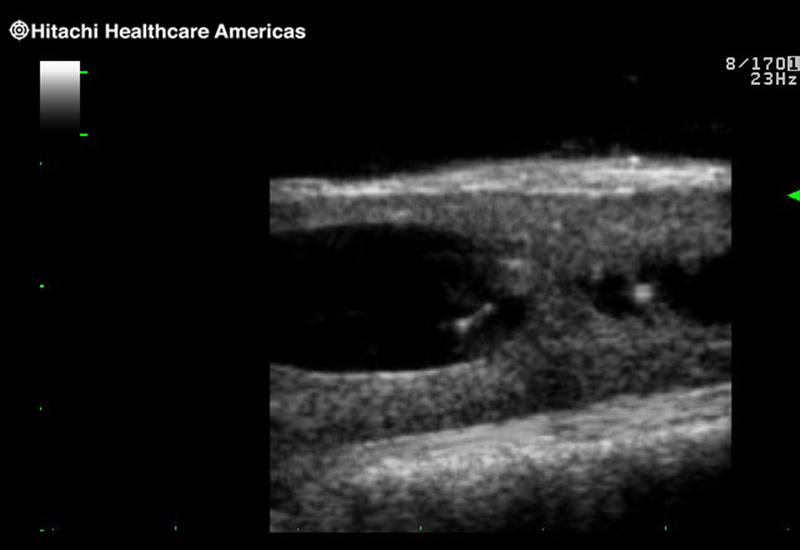

Our smallest footprint allows for enhanced contact in tight spaces

Our newest probe, the L51K allows the surgeon access to difficult-to-reach areas that no other probe on the market can go. The unique design and proximal location of the attaching mechanism provides full wrist articulation and easier grasp and release.

The next level in Robotic Ultrasound

Full wrist articulation with optimized functional length.

A critical function of robotic ultrasound guidance is tumor margin identification. Fujifilm's family of robotic probes all have the optimum location of the attaching mechanism that allows for full wrist articulation of the probe. The result is an increased confidence that the tumor margins have been completely identified.